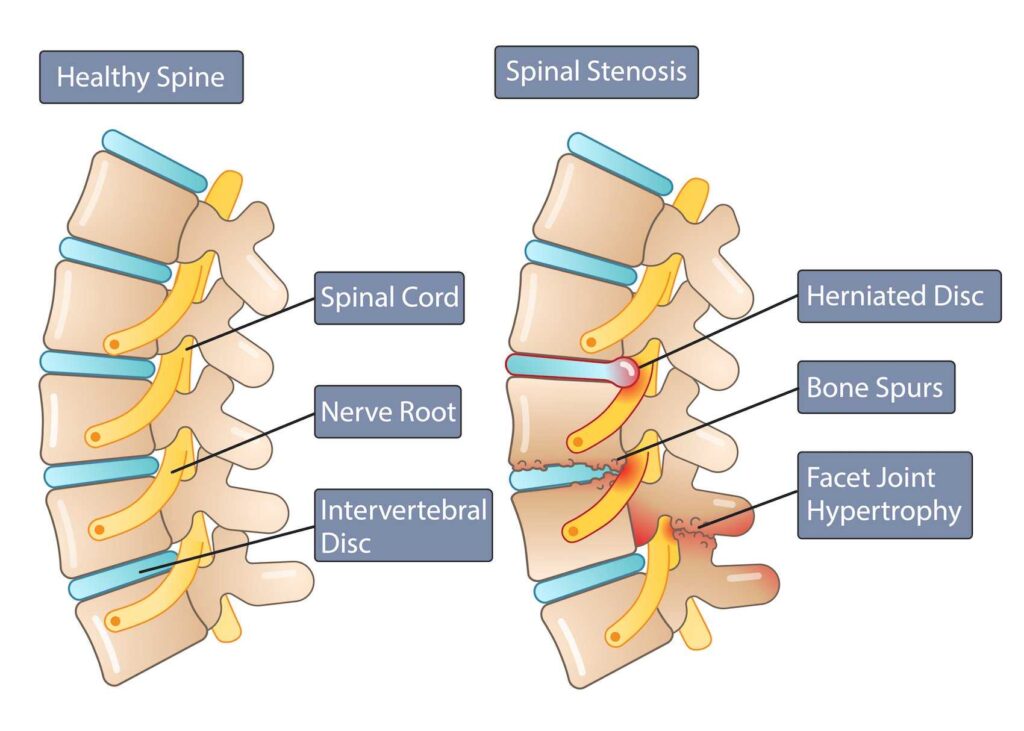

Lumbar Canal Stenosis

Lumbar canal stenosis is a common spinal condition that occurs when the spinal canal..